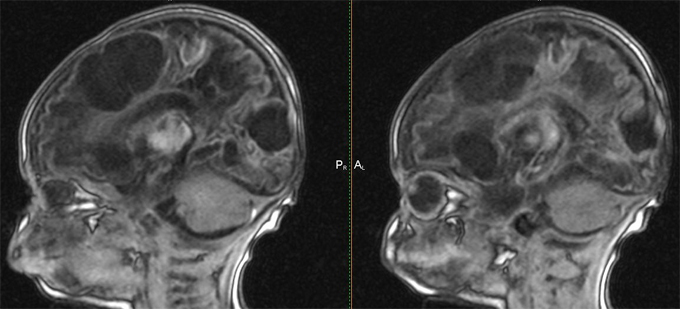

Внутричерепная гипотензия: КТ-исследования и их интерпретация

Раздел: Образы вокруг